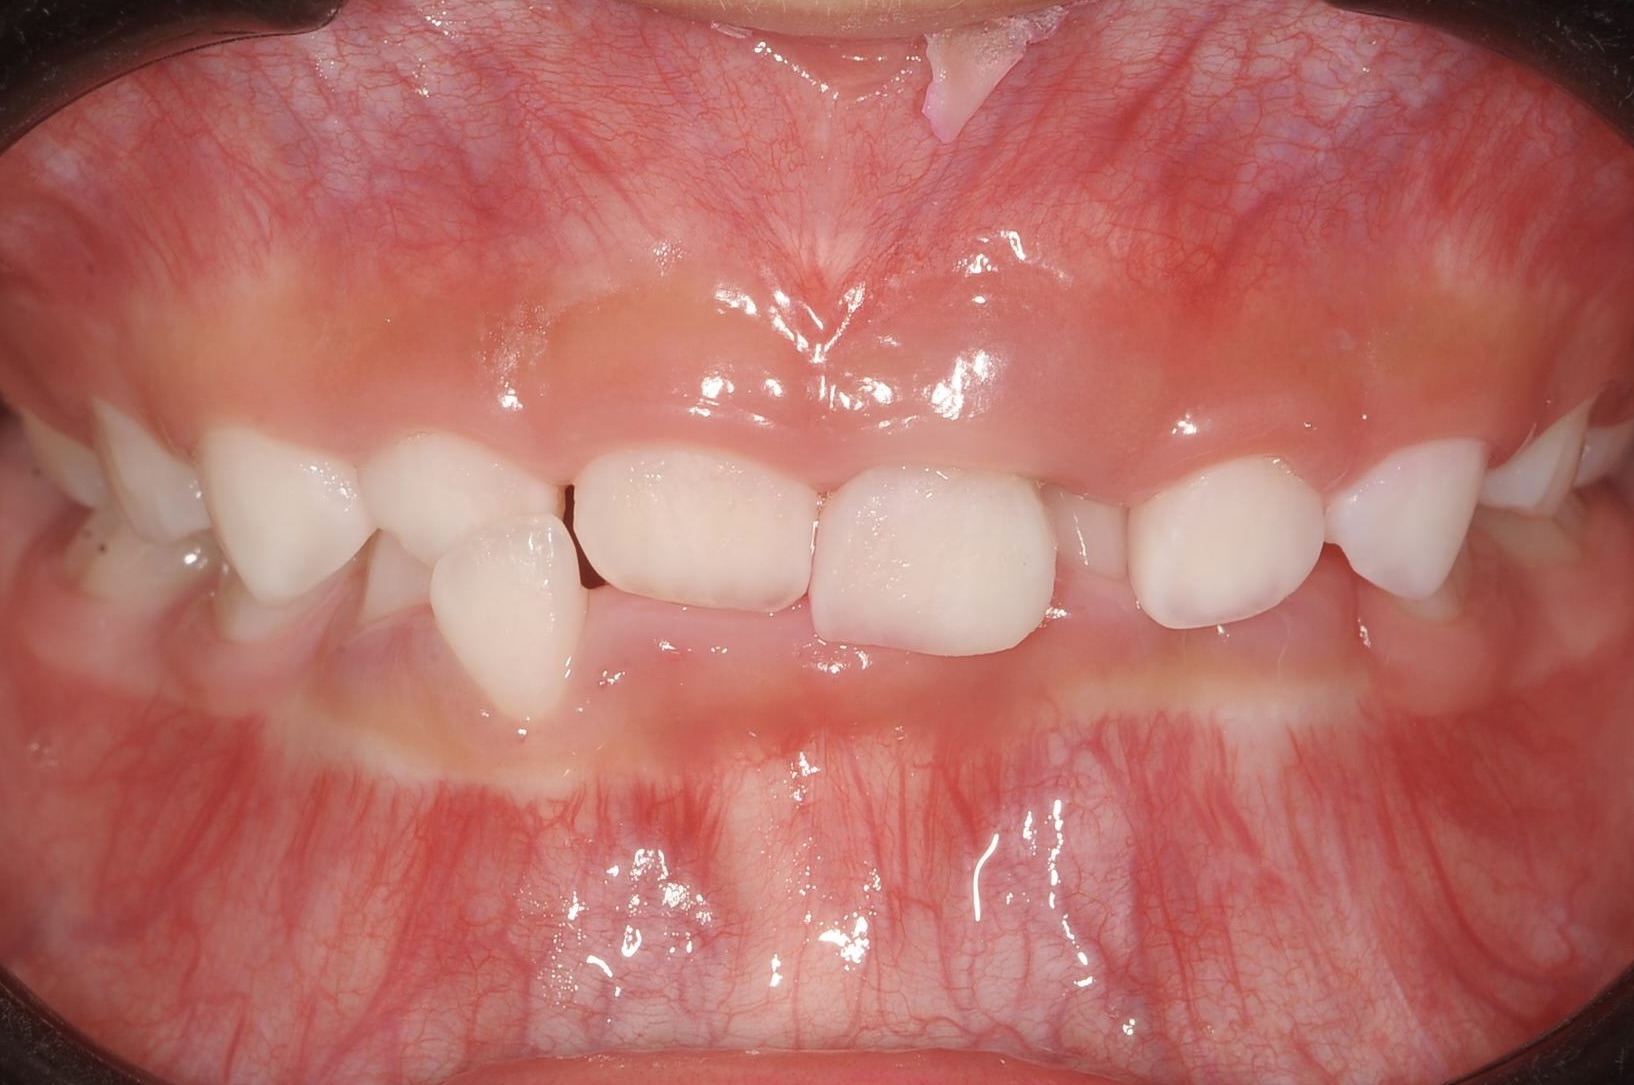

乳歯と永久歯が混在する6歳頃〜11歳

乳歯と永久歯が混在する時期に行う矯正歯科治療です。

顎や口腔機能の成長・発育といった「土台」から正しい歯並びへ導く、お子様ならではの矯正治療が行えます。

負担を考えた、お子様一人ひとりに適切な装置を使用します。